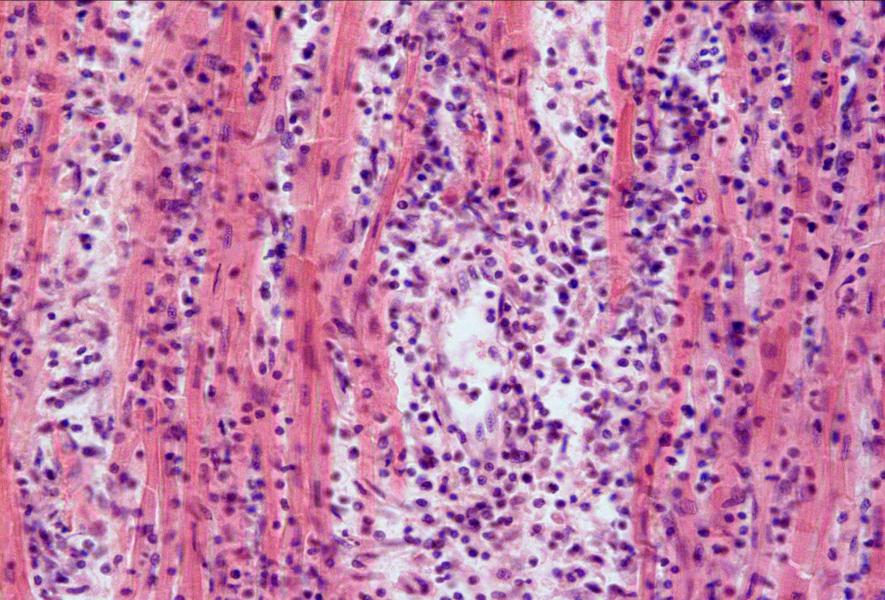

Межуточный миокардит: гистологические исследования

Раздел: Идеи и советы